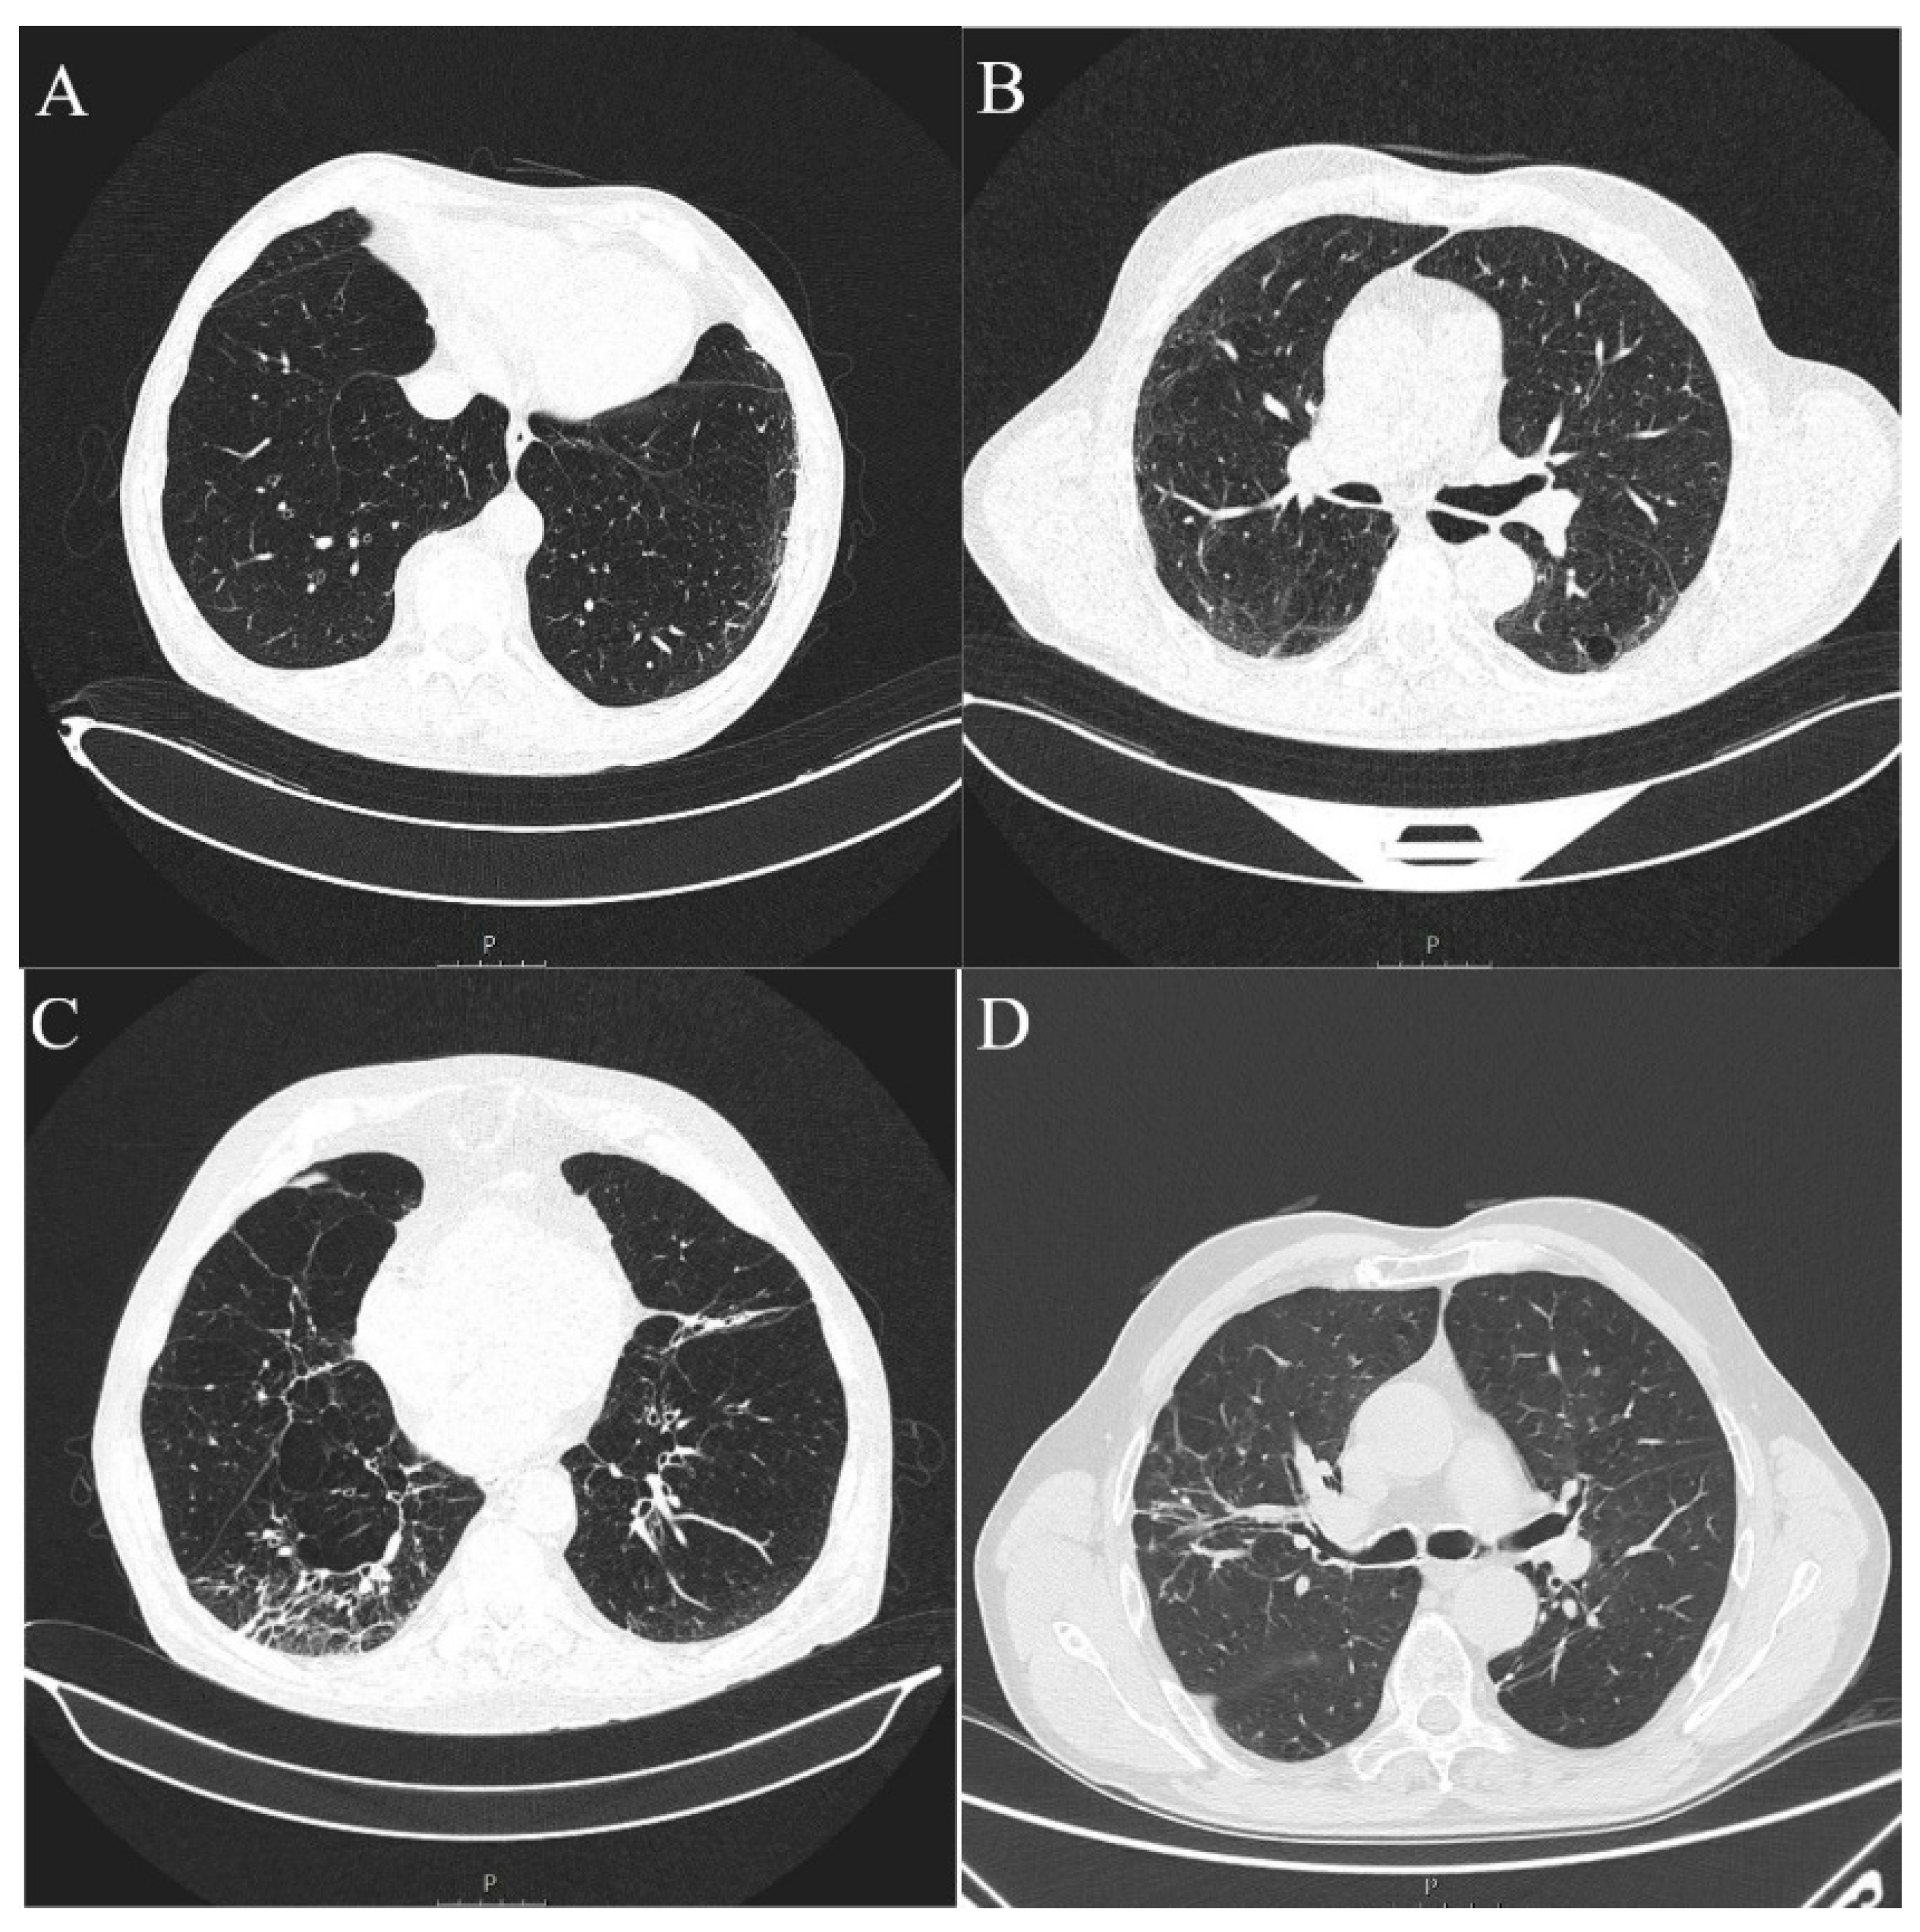

Figure 4.

Axial MSCT scans of pretreatment lung parenchyma demonstrating typical ILA findings in HNSCC patients (A). Unilateral subpleural non-fibrotic type characterized by subpleural reticulations surrounded by areas of GGO (B). Bilateral subpleural non-fibrotic changes manifesting as subpleural reticulations surrounded by areas of GGO and sporadic non-emphysematous cysts (C). Unilateral subpleural fibrotic changes in the right lung, manifesting as traction bronchiectasis and bronchiolectasis with parenchymal distortion and zones of GGO. Contralateral lung shows mild traction bronchiectasis and subpleural reticulations (D). Unilateral non-subpleural, traction bronchiectasis with architectural distortion surrounded by small zones of GGO. Two small intraparenchymal calcifications in close proximity were not classified as ILA.

ILA changes were most prevalent in the lower lung zones (n = 11, 73.3%), followed by upper zones (n = 6, 40.00%) and least reported in the middle lung zones (n = 2, 13.3%), which was significantly different (p = 0.0045). The most commonly reported ILA subtype was subpleural non-fibrotic (n = 9, 60%), followed by subpleural fibrotic (n = 4, 26.67%) and non-subpleural (n = 2, 13.33%) (p = 0.0354) (Table 3, Figure 3 and Figure 4). Reticulations were the most frequently described pattern in almost every patient with ILA changes (n = 14, 93.3%) (p < 0.0001). Other ILA patterns were non-emphysematous cysts (n = 8, 53.33%), distortion with traction bronchiectasis (n = 6, 40.00%) and ground glass opacity in four (26.67%) patients. Distortion with honeycombing was not reported in any of the patients (Table 4, Figure 3 and Figure 4).